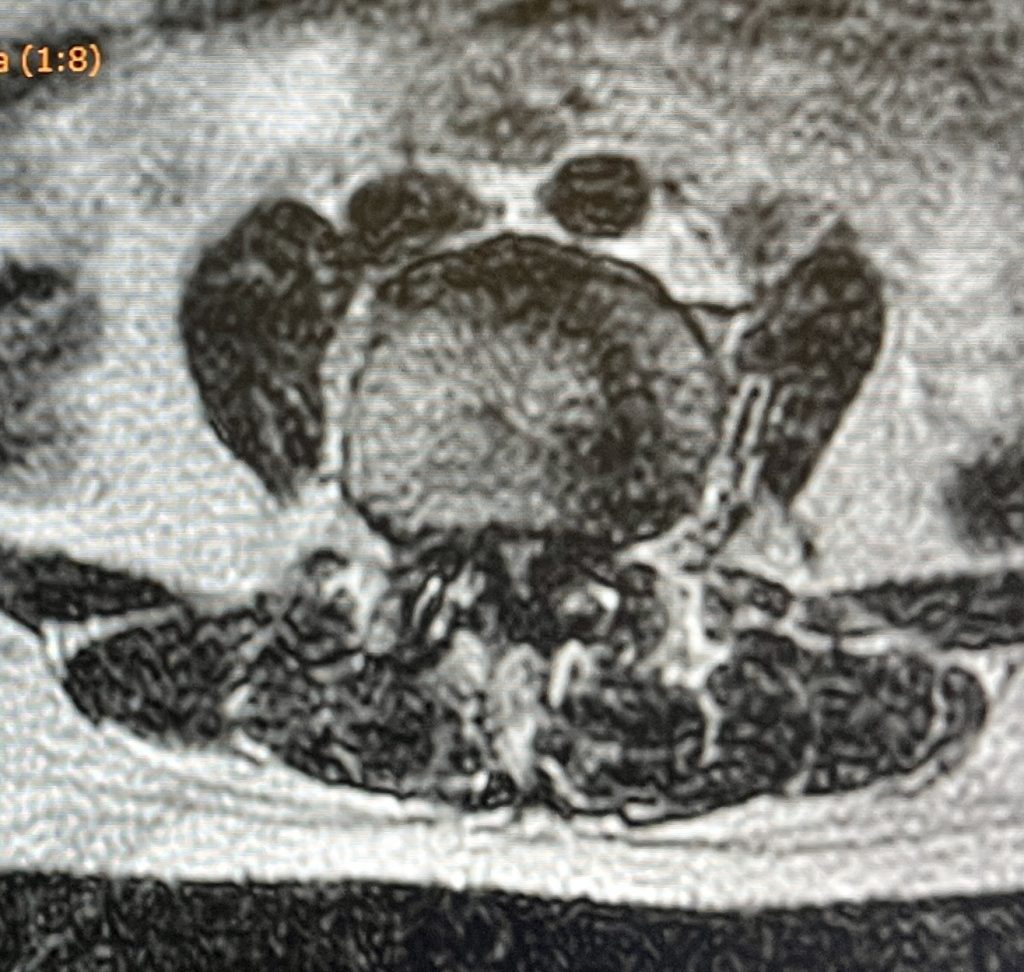

La estenosis de canal lumbar se produce como consecuencia del cierre progresivo de canal espinal, secundario a procesos degenerativos en el disco, las articulaciones facetarias y ligamentos intervertebrales. Estos cambios conllevan a la larga el atrapamiento de raíces nerviosas dentro del canal lumbar, que se manifiestan clínicamente como dolor ciático, dolor en los glúteos y dificultad para la deambulación prolongada.

El tratamiento consiste en descompresión del canal asociado o no a estabilización mediante la fusión vertebral . La descompresión implica la extracción de partes de las vértebras, ligamentos o discos protuberantes que están causando la compresión de los nervios o de la médula espinal. En muchos casos puede realizarse mediante técnicas mínimamente invasivas microquirúrgicas o endoscopias.